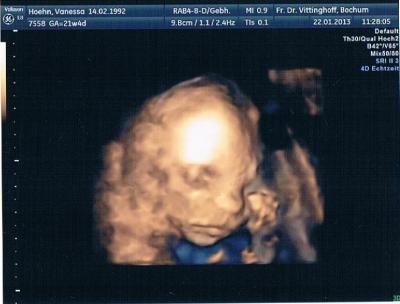

Da bin ich wieder und ich bin verliebt Mein kleiner Schucki ist fast 25 cm lang und wiegt jetzt 409 g, also ist er in 4 Tagen ganze 3 cm und 60 g gewachsen!! Er hat sich die ganze Zeit eingekuschelt, dann am Ende hat er gegen meinen Bauch getreten und man hat es von außen das 1. Mal gesehen... Es ist übrigens alles gut, er hat keine Herznebengeräusche (wie ich). Ich bin so glücklich Hier noch ein Bild von meinem Söhnchen

Bild zu Määäääädels, bin wieder daaaaaaa! :) - Forum für Mai - Mamis